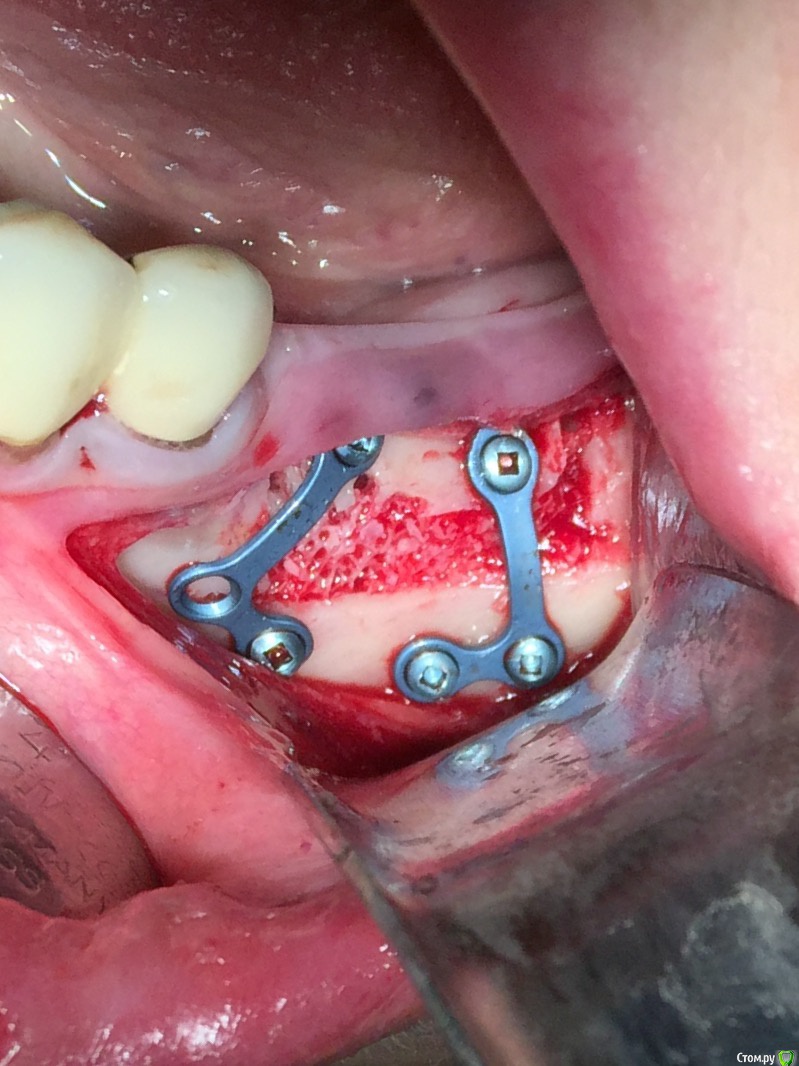

an_ver Опубликовано 16 января, 2016 Поделиться Опубликовано 16 января, 2016 Винты 1,5 мм самосверлящие,Конмет?Длина какая? L пластины длинные? Ссылка на комментарий

Глеб Митрофанов Опубликовано 16 января, 2016 Автор Поделиться Опубликовано 16 января, 2016 Винты 1,5 мм самосверлящие,Конмет?Длина какая? L пластины длинные? Да , винты 1,5 мм самосверлящие конметовские длина верхние 5 мм , нижние 4 мм , пластины не длинные , по одному сегменту отпилил еще 1 Ссылка на комментарий

Глеб Митрофанов Опубликовано 16 января, 2016 Автор Поделиться Опубликовано 16 января, 2016 Что за блок вставлен ? SP-BLOCK osteobiol 1 Ссылка на комментарий

an_ver Опубликовано 17 января, 2016 Поделиться Опубликовано 17 января, 2016 (изменено) Верхние винты насквозь через SP и в свою кость? Как горизонтальный распил делаете, пальцем с язычной, тактильно? Пилите УЗ?И есть ли снимок до? Изменено 17 января, 2016 пользователем an_ver Ссылка на комментарий

Глеб Митрофанов Опубликовано 19 января, 2016 Автор Поделиться Опубликовано 19 января, 2016 Верхние винты насквозь через SP и в свою кость? Как горизонтальный распил делаете, пальцем с язычной, тактильно? Пилите УЗ?И есть ли снимок до?Верхние винты в свою кость , распил делал УЗ , язычно контроль пальпаторно , да и чувствуется , что прошёл язычную кортикалку . Снимок до конечно есть . Ссылка на комментарий